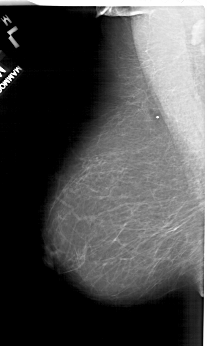

A_1150_1.LEFT_CC

LEFT_CC LINES 6196 PIXELS_PER_LINE 3571 BITS_PER_PIXEL 12 RESOLUTION 43.5 NON_OVERLAY